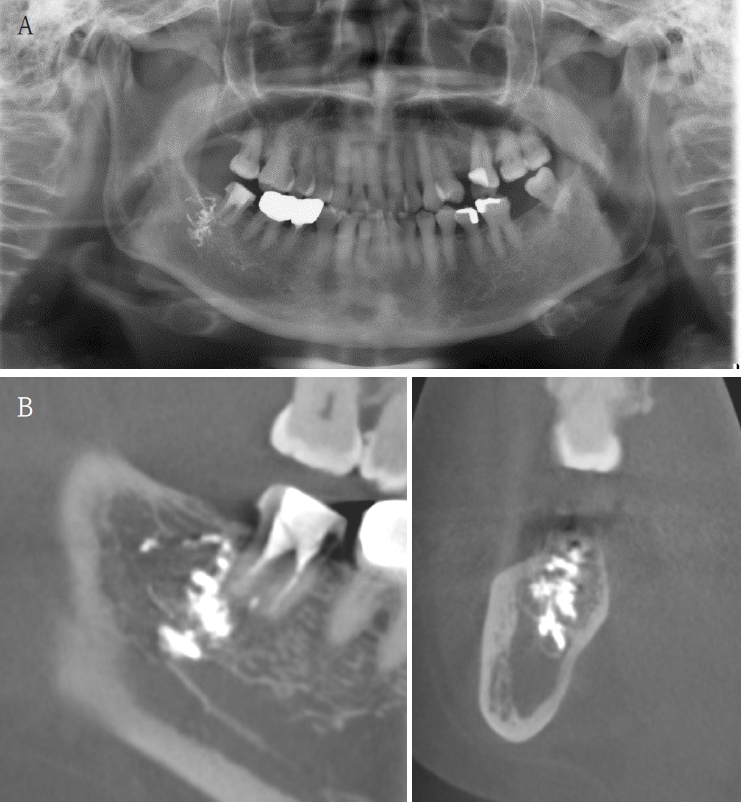

A 61-year-old female presented with intermittent right mandibular swelling and pain after root canal therapy was done using EndoSeal MTA 5 months ago. A panoramic radiograph, CBCT and bone scan confirmed material extrusion and mild localized bone changes (Fig. 4). Initial neurologic evaluation demonstrated nearly normal sensory function, with Visual Analog Scale (VAS) 4 discomfort. Surgical curettage was performed under local anesthesia. A post-operative panoramic radiograph confirmed the substantial removal of the foreign body (Fig. 5). Postoperatively, the patient reported significant improvement at both the one- and two-month follow-ups. Due to full symptom resolution, no follow-up neurosensory testing was performed.

Figure 4.

A. Pre-op panoramic radiograph of Case 3 patient. B. Pre-op CBCT of Case 3 patient. C. Pre-op bone scan of Case 3 patient